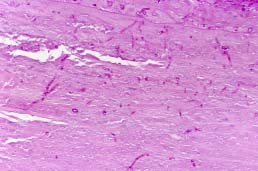

Las técnicas de tinción necesarias para una correcta identificación de las características del hongo (Tabla 1) son: Hematoxilina-eosina (Fig.2) y de modo más específico, Metenamina-plata de Gomori (Fig.3) o Grocott y ácido periódico de Schiff (PAS) (Fig.4); otra técnica de plata, de Masson-Fontana, ha demostrado ser más útil que otras para la identificación de las características de los hongos Dematiáceos (hongos pigmentados), causantes con frecuencia de la Sinusitis fungal alérgica, ya que tiñen su pared y la contrastan mejor (4). Estos hongos están presentes en el moco eosinófilo laminado, procedente de los senos paranasales (Fig.5); estas muestras de material mucoide, sin tejido, deben ser teñidas siempre, para detectar las formaciones micóticas (Fig.6).

02p.jpg (33071 bytes)

Fig.2